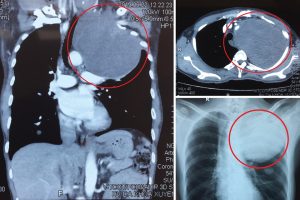

Ngày 26/6/2019, Khoa Phẫu thuật Tim mạch và Lồng ngực – Bệnh viện Đa Khoa Xuyên Á TP.HCM vừa phẫu thuật cho bệnh nhân có u trung thất kích thước khổng lồ, xâm lấn rộng các cơ quan ở đỉnh lồng ngực trái.